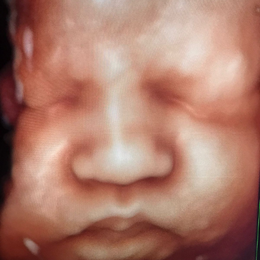

Ecografía del corazón fetal en 4D

Ocho de cada mil bebes nace con algún defecto cardíaco congénito. Estas anomalías se producen por un desarrollo anormal del corazón durante el embarazo y pueden consistir en defectos de sus paredes o válvulas, o de los vasos sanguíneos que entran o salen de él.